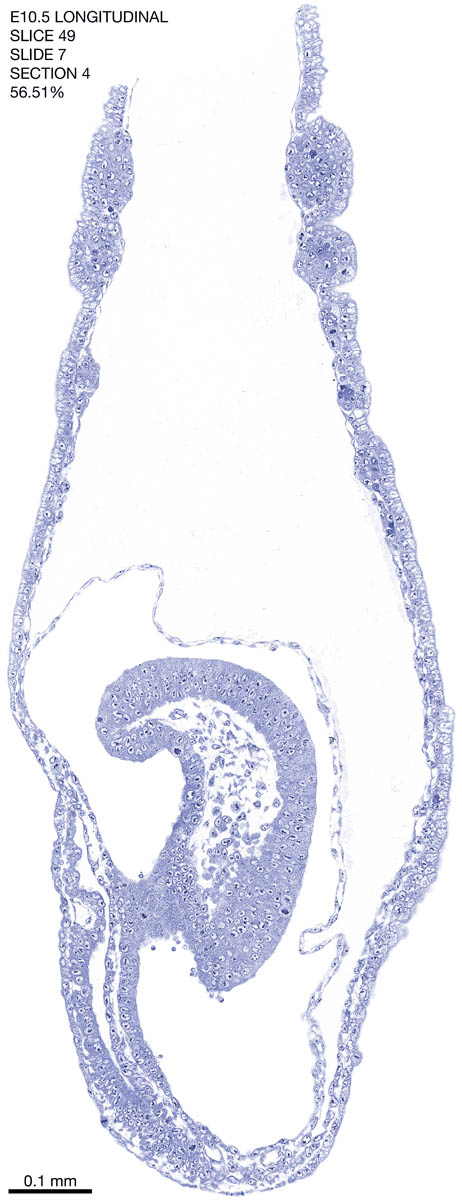

E10.5 Longitudianal Archive This page contains jpg files of ALL SLICES (each 3µm thick) that were scanned of the E10.5 longitudinally cut specimen. Download: Large | High Res Download: Large | High Res Download: Large | High Res Download: Large | High Res Download: Large | High Res Download: Large | High Res Download: Large | High Res Download: Large | High Res Download: Large | High Res Download: Large | High Res Download: Large | High Res Download: Large | High Res Download: Large | High Res Download: Large | High Res Download: Large | High Res Download: Large | High Res Download: Large | High Res Download: Large | High Res Download: Large | High Res Download: Large | High Res Download: Large | High Res Download: Large | High Res Download: Large | High Res Download: Large | High Res Download: Large | High Res Download: Large | High Res Download: Large | High Res Download: Large | High Res Download: Large | High Res Download: Large | High Res Download: Large | High Res Download: Large | High Res Download: Large | High Res Download: Large | High Res Download: Large | High Res Download: Large | High Res Download: Large | High Res Download: Large | High Res Download: Large | High Res Download: Large | High Res Download: Large | High Res Download: Large | High Res Download: Large | High Res Download: Large | High Res Download: Large | High Res Download: Large | High Res Download: Large | High Res Download: Large | High Res Download: Large | High Res Download: Large | High Res Download: Large | High Res Download: Large | High Res Download: Large | High Res Download: Large | High Res Download: Large | High Res Download: Large | High Res Download: Large | High Res Download: Large | High Res